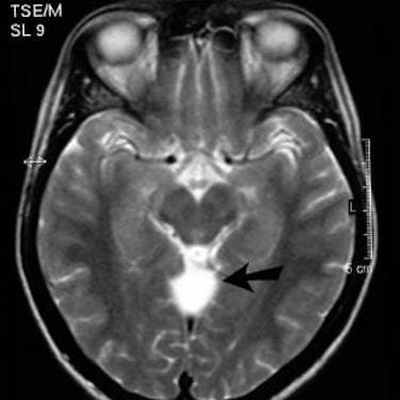

МРТ головного мозга - киста прозрачной перегородки

Киста прозрачной перегородки – это вид арахноидальной кисты, когда жидкость скапливается между пластинками прозрачной перегородки мозга. Они могут носить как приобретенный характер из-за черепно-мозговых травм или инфекций, так и врожденный характер. Поскольку эти кисты локализуются в самом безопасном месте, их появление практически никогда не сопровождается неврологической симптоматикой. В подавляющем большинстве случаев такие кисты не требует ни оперативного, ни медикаментозного лечения. Пациентам с выявленной кистой прозрачной перегородки необходимо ходить на прием к неврологу и проверять результаты свежего шестимесячного МРТ головного мозга.

| Киста прозрачной перегородки на МРТ | Арахноидальная киста на МРТ |